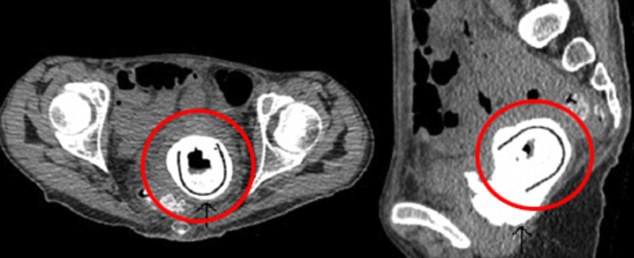

La donna trentottenne aveva deciso di andare in ospedale dopo che da qualche tempo lamentava perdita di peso, stanchezza e tremori. I medici la hanno sottoposta a vari esami, ma quello che li ha scioccati sono stai i raggi X: dalla lastra infatti si vedeva un oggetto lungo circa 5 cm presente nella vagina della donna. Si trattava di un vibratore, che la donna ha raccontato di non avere più visto negli ultimi dieci anni, e che era convinta di avere perso. Pertanto i medici suppongono che l’ultima volta che la donna ha utilizzato il giocattolo erotico, lo abbia “dimenticato” all’interno della vagina. Peraltro, sembra che lei e il partner avessero bevuto molto quella sera.

La presenza dell’oggetto ha alla fine lesionato l’uretra della donna, causandole un infezione che ha spinto la donna a recarsi in ospedale.